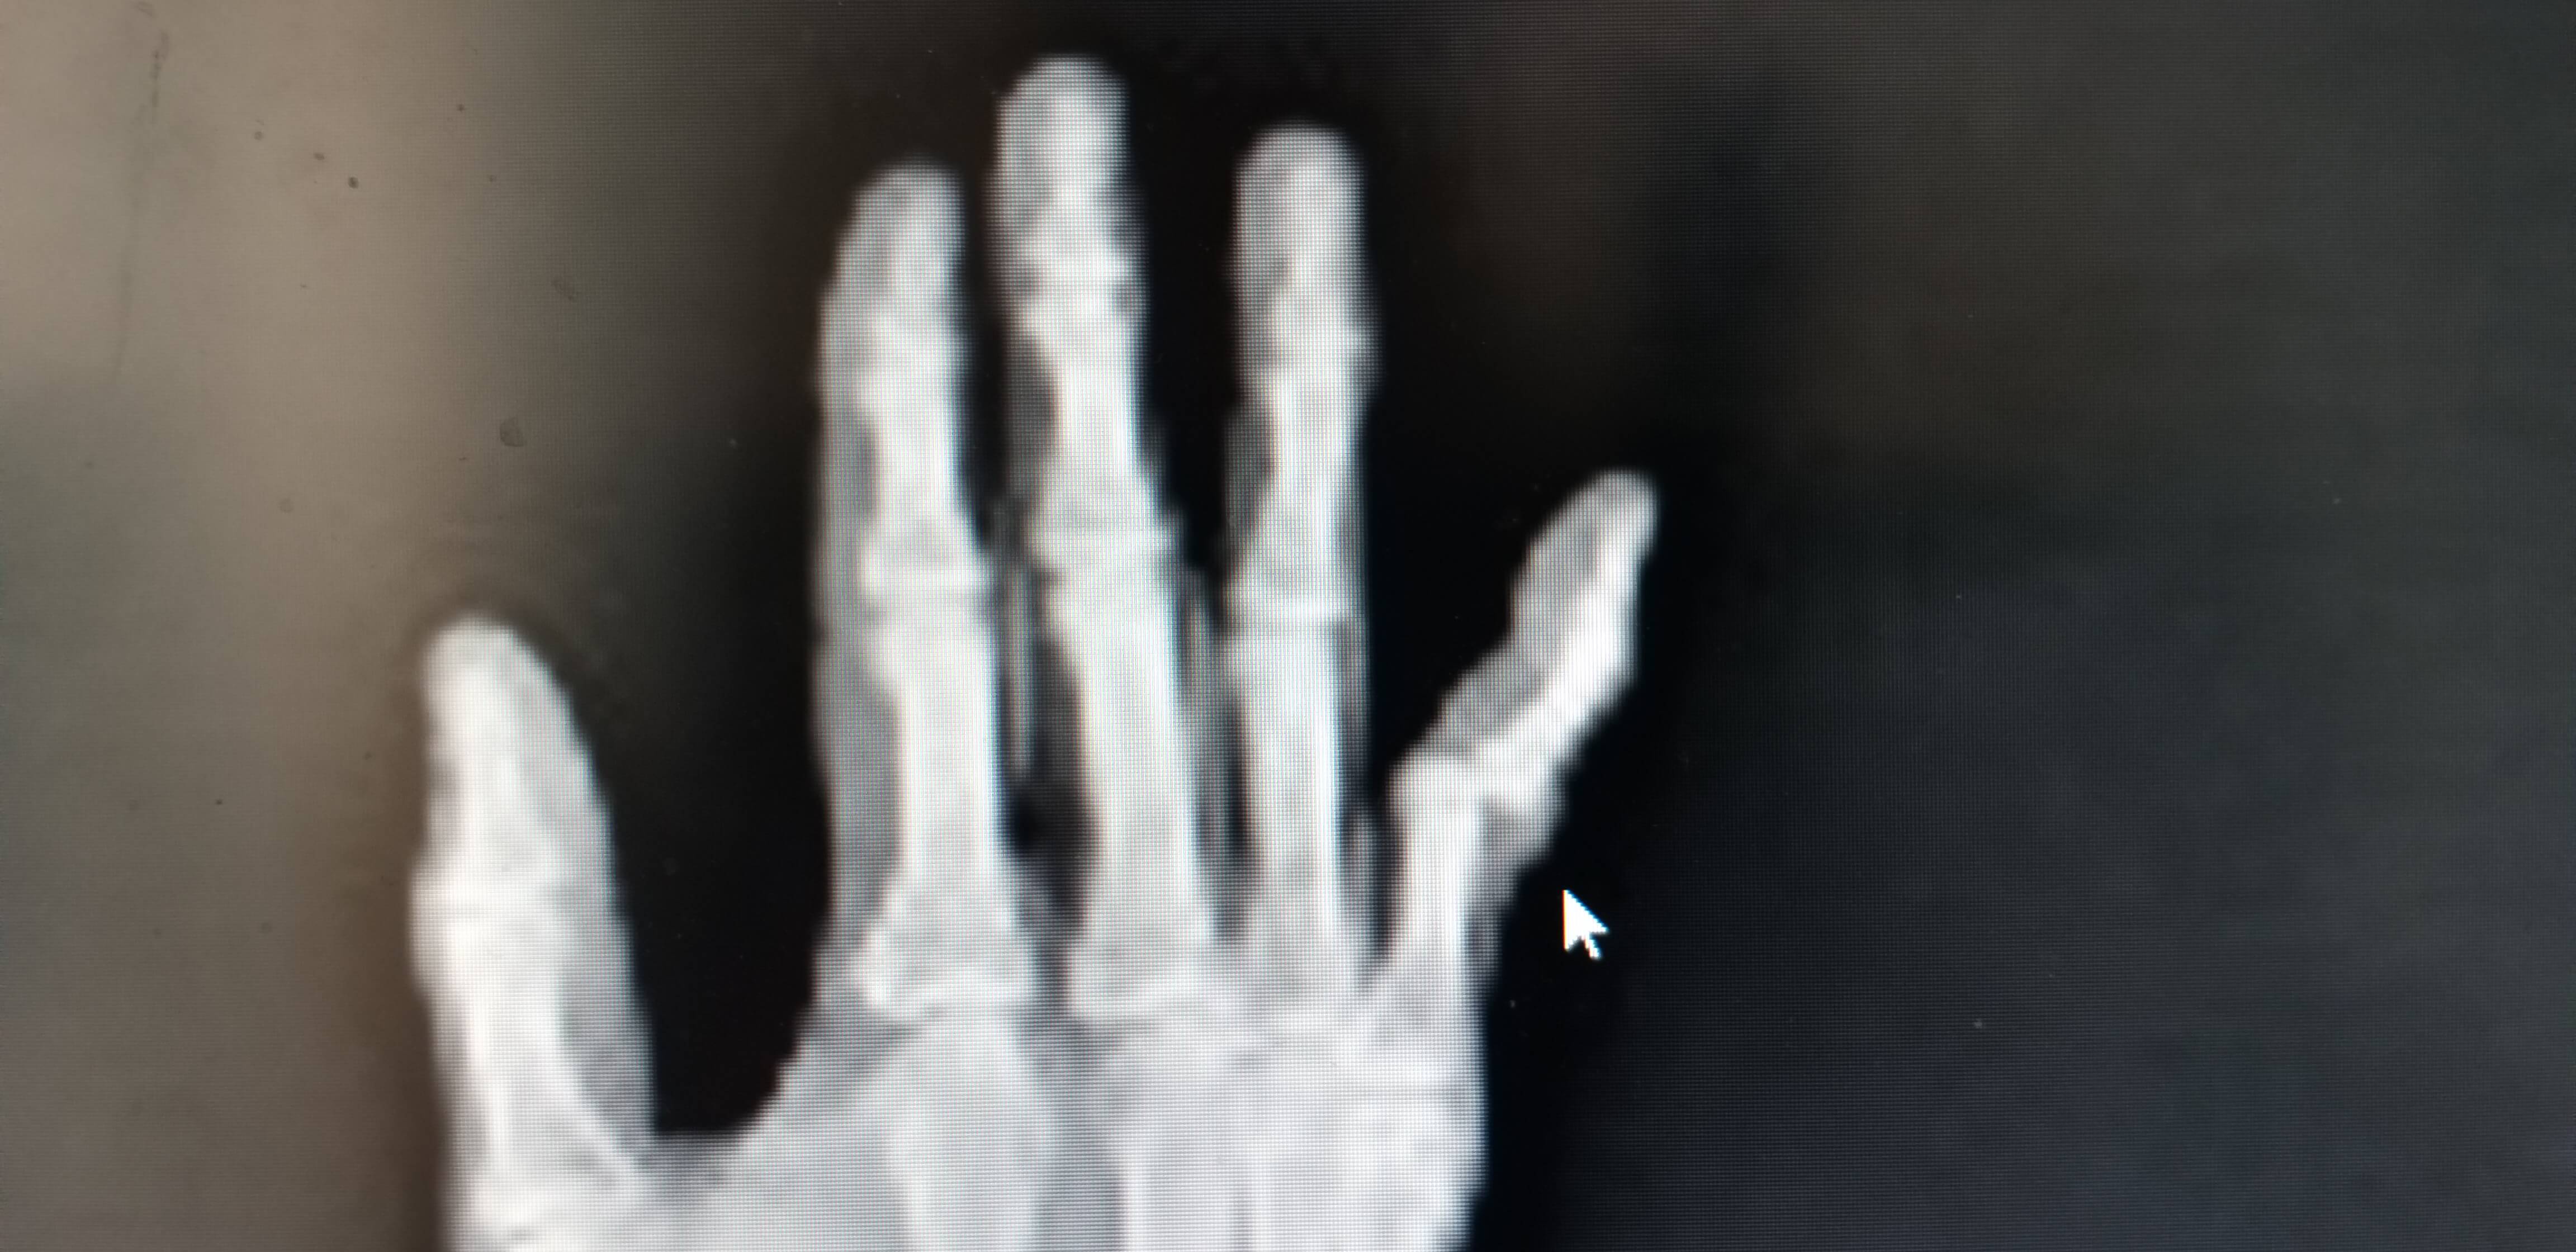

다친사진 및 경과를 모두 설명드렸고 이전병원에서의 사진을 보여드렸고 다시 X-RAY 사진촬영을 하신후 진단받은 결과로는 손가락 인대파열은 엄지손가락 말고는 기본적으로 보존적 치료를 먼저 한다고 말씀하셨습니다.

뼈조각은 크기나 형태에 따라 문제가 발생되지 않아보이고 새끼손가락의 배열도 잘맞아서 수술은 권유하지 않았습니다.

한달동안 부목을 손가락에 고정시키고 상태를 확인해보자고 말씀하셔서 이게 도대체 무슨일인지 마음속으로는 다행이라고 생각하고 몇번을 수술안해도 되냐고 물었습니다.